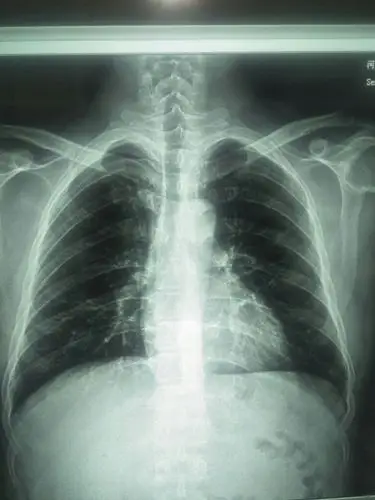

帮忙看看这ct片!

医生帮看一下这个ct片子

帮忙看看ct片

【读片】看看这几张胸部ct片(无病史只看片) [病例帖]